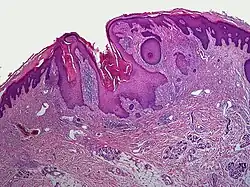

A dilated pore, also known as a dilated pore of Winer, is a cutaneous condition characterized by a solitary, prominent, open comedo on the face or upper trunk of an individual.[1]: 675  Louis H. Winer is credited with discovering the dilated pore. [2][3]